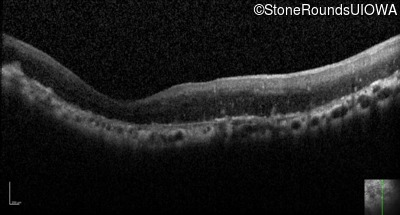

Optical Coherence Tomography - Right - Light Perception

Exemplar